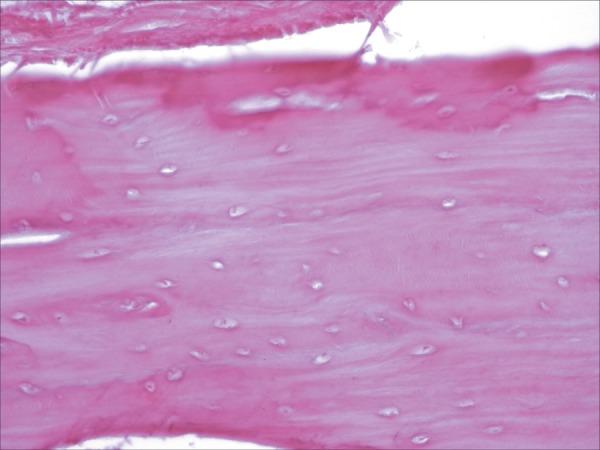

In the two-way analysis of variance, the effect of group and time was statistically significant (p<0.001). Additionally, a statistically significant interaction between group and time was observed (p<0.001). Control animals showed normal growth and development of the temporal region. In the experimental group, the change in direction of the force vector of the mandible induced significant changes in the temporal bone, with a bone modeling process, which suggests growth of this cranial structure.

The methodology used in this experiment allows us to conclude that the change in direction of the force vector of the mandible in relation to the skull base induces remodeling and modeling processes in the temporal bone. The resumption of normal oral functions after bone healing of the mandibular fracture appears to increase cell activation in the remodeling and modeling of the temporal bone structure. The observation of areas of temporal bone modeling shows the relevance of further investigation on the correlation between the joint structures and craniofacial growth and development.